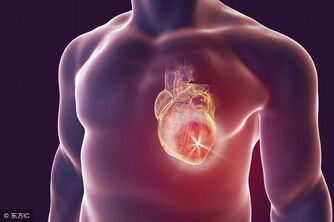

1、心

研究發現,健康的愛發脾氣者罹患心髒病而死亡的機率高出19%。生氣時,心臟的收縮力加強,心跳加速,大量的血液湧向心臟,心臟則需要加倍工作。這時就會出現心率不齊、心肌缺血、胸悶、心慌,甚至誘發心絞痛和心肌梗塞。